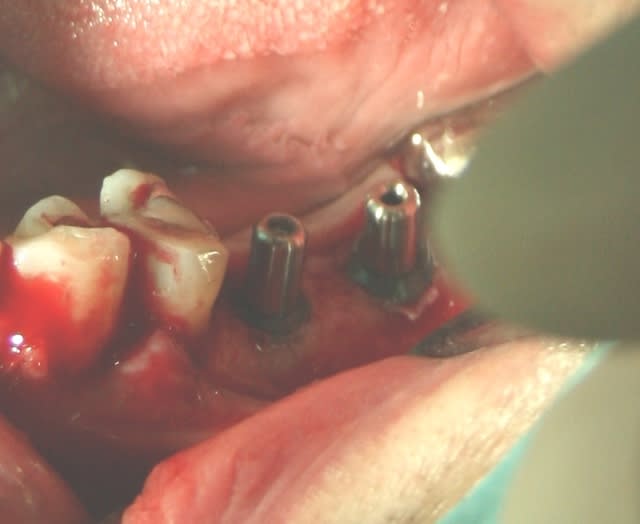

Mise en place de 2 implants IDI Idcam , très bonne impression , forage hypersimplifié ( 4 forets pour du 5.2),et sécurisé grâce aux forets à butée, excellente sensations lors de la mise en place à la clef à cliquet à la position souhaité / à l'os crestal.

bravo pour ta pose, christophe13, c'est bien propre.